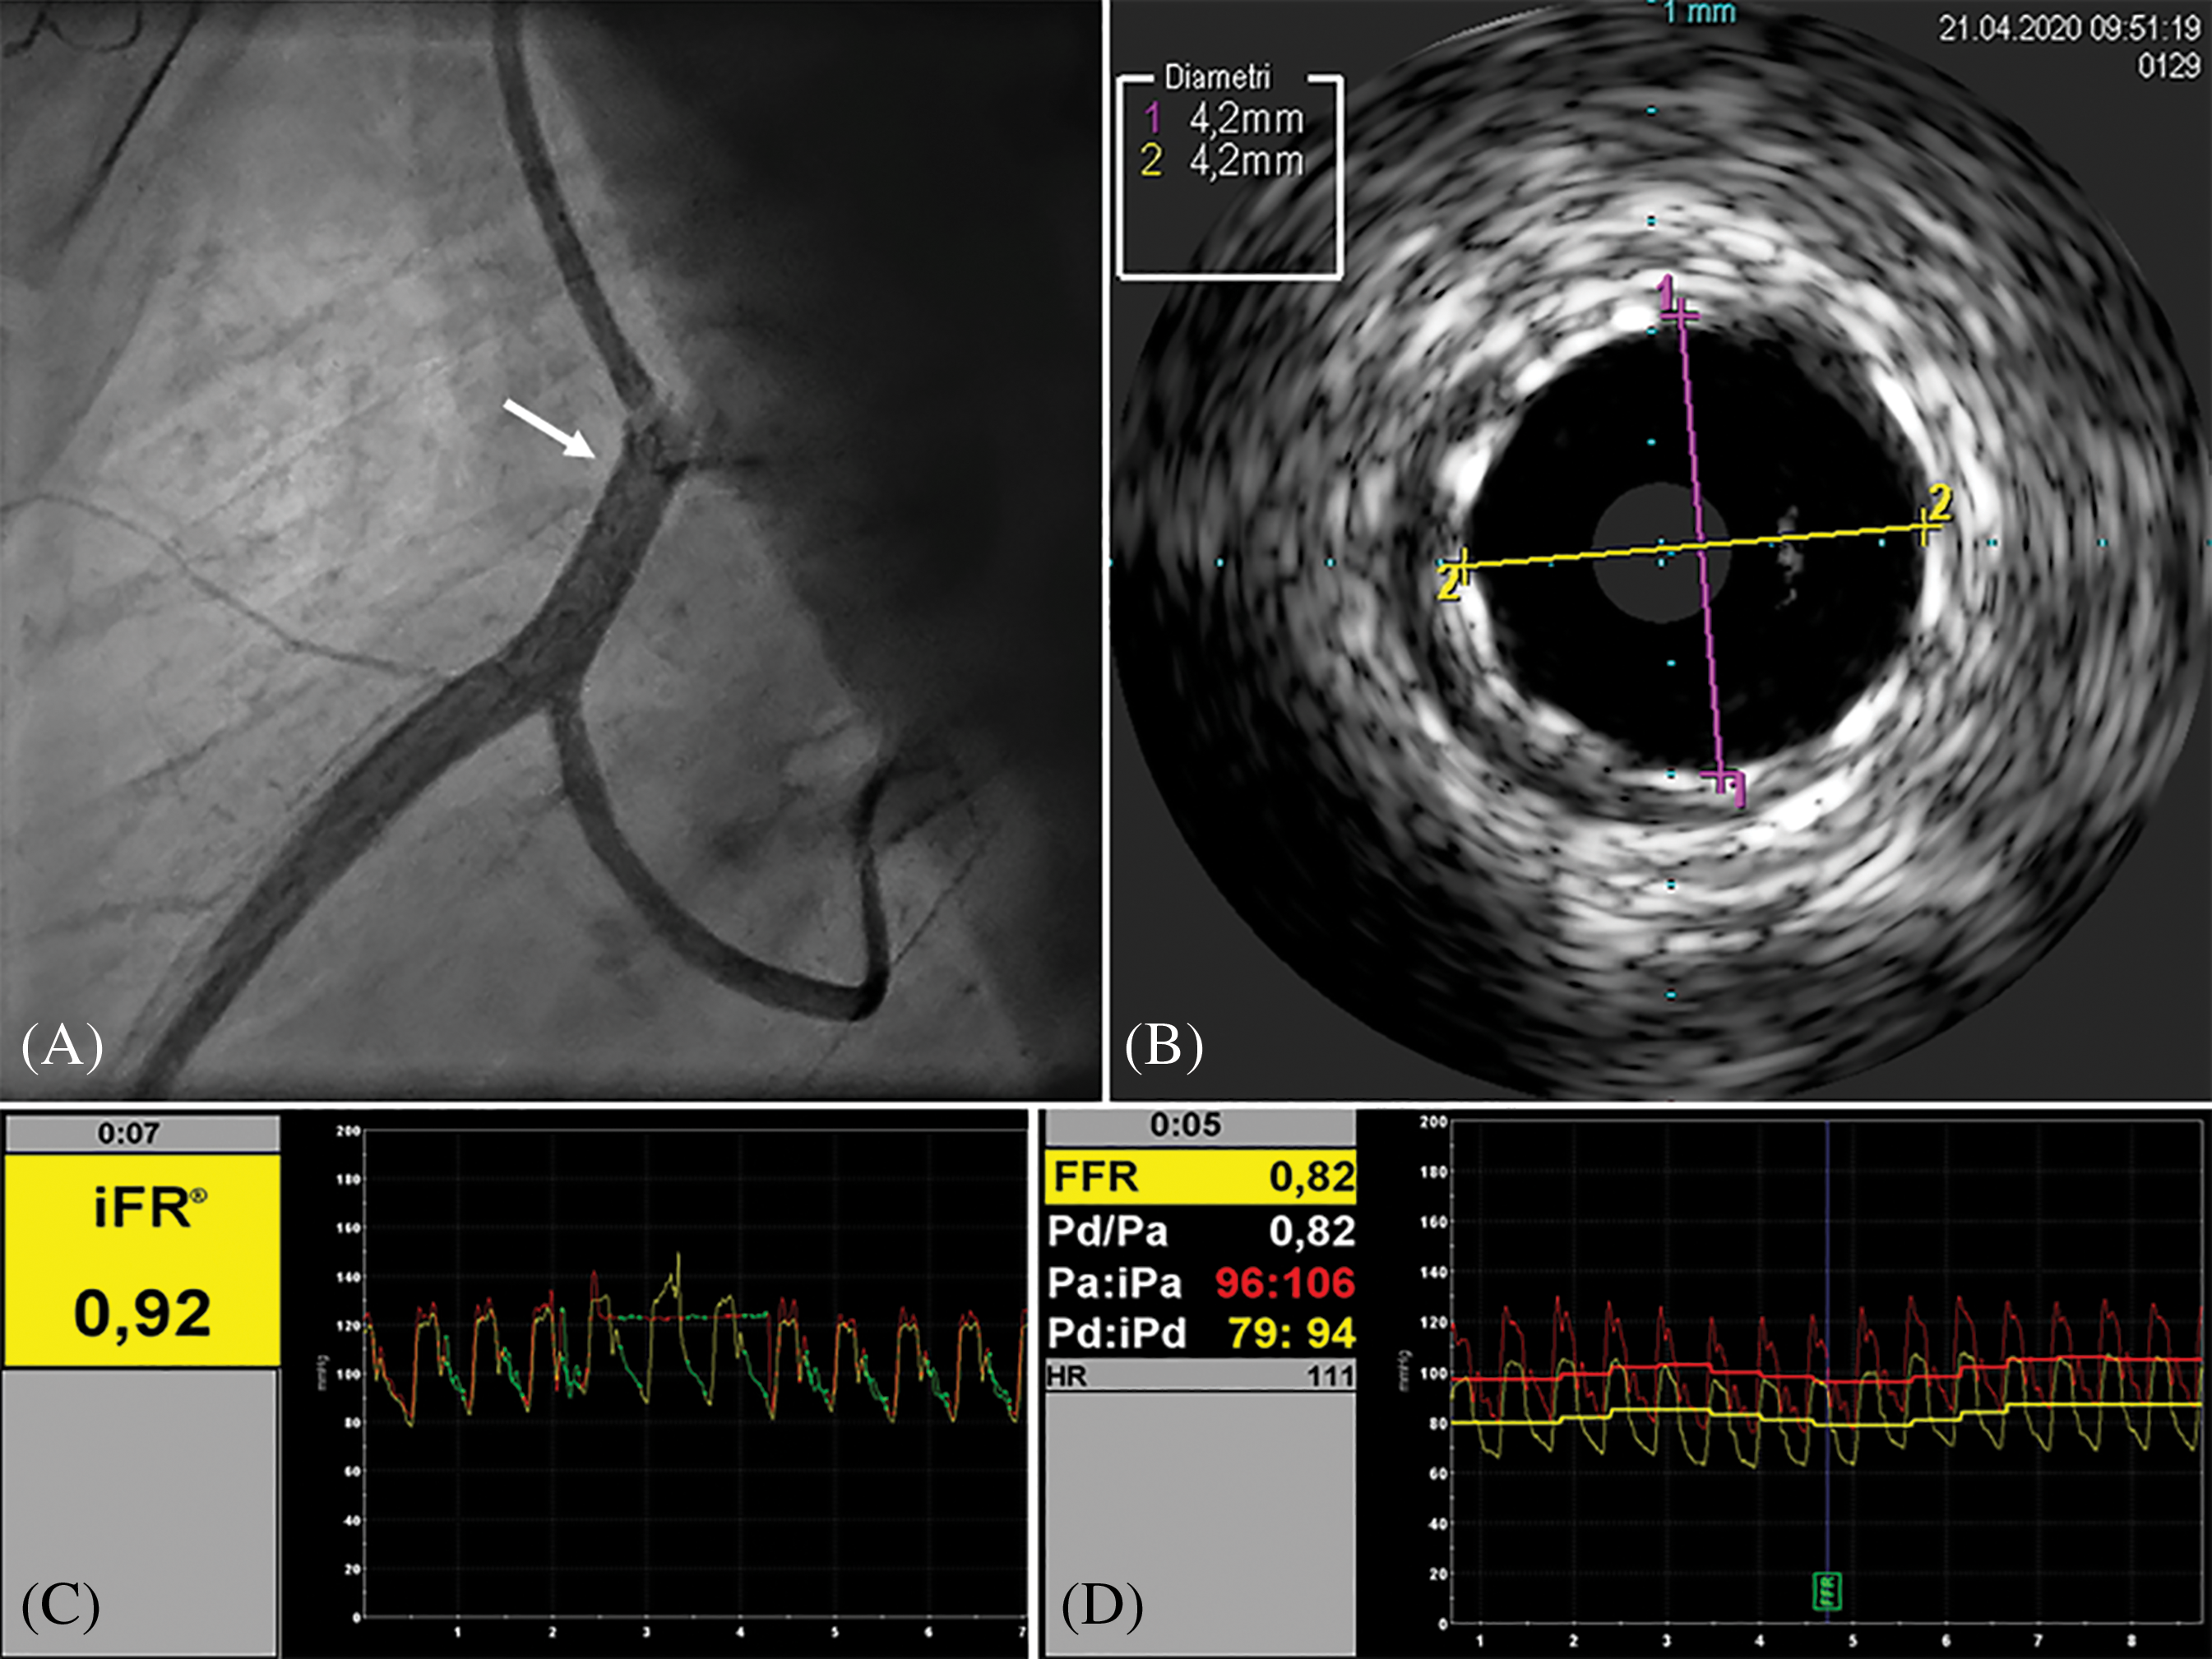

A 17-year-old male, body weight 73 kg, height 190 cm, was electively admitted in our Hospital to undergo invasive coronary angiogram. He had a past history of D-TGA, ventricular septal defect (VSD) and anomalous origin of the left circumflex coronary artery (LCx) from the right coronary artery (RCA). At the age of 2 weeks, he underwent surgical repair with ASO, LeCompte maneuver, coronary artery translocation and VSD closure. As per local protocol to assess coronary anatomy after ASO, at 10 years of age he was referred for elective coronary angiography, showing a 50% lumen stenosis at the origin of RCA. Subsequently, he underwent myocardial perfusion scintigraphy (SPECT) at rest and under pharmacological stress with adenosine infusion, which demonstrated a small perfusion defect of the mid-segment of the anterior wall under stress. Unfortunately, given the presence of right bundle branch block on the electrocardiogram (EKG), repolarization abnormalities assessment during the stress were not reliable for myocardial ischemia diagnosis. Considering the un-correlation of the two diagnostic exams regarding ischemic territory and the absence of symptoms, the decision made was to not treat the stenosis and to follow-up the patient yearly with electrocardiogram (EKG), transthoracic echocardiogram (TTE), and exercise-stress testing. At 17 years of age he repeated a SPECT at rest and under physical exercise stress test, which showed hypo-perfusion of mid- and basal segments of both anterior and inferior wall under stress. TTE showed preserved left ventricle ejection fraction (LVEF biplane 55%), reduced LV global longitudinal strain (GLS −15%), more evident in the inferior and posterior septum wall, and preserved right ventricular (RV) function. Following multidisciplinary team discussion, the patient was admitted for elective coronary angiogram. On admission patient was preloaded with 600 mg of clopidogrel PO. Through femoral artery access, selective angiogram showed dominant RCA with a 50% ostial stenosis (Fig. 1A). IV unfractioned heparin 5000 UI was administered. Thereafter, intravascular ultrasound (IVUS) was employed to better characterize the stenosis from the anatomical standpoint. IVUS (Eagle Eye Platinum ST®, Philips Volcano,) showed mild reduction of RCA ostium minimal lumen area (MLA 8.8 mm2) with mild and eccentric neo-intimal proliferation, in absence of clear atherosclerotic plaque (Fig. 1B). Subsequently, we performed a functional analysis of the stenotic segment using a coronary pressure wire (Verrata Plus®, Philips Volcano). Firstly, we measured the instantaneous wave-free ratio (iFR) which resulted 0.89, falling in the so-called “grey zone”, and then the fractional flow reserve (FFR) pre- and post-adenosine induced (400 mcg intracoronary) hyperaemia which was 0.89 and 0.63 respectively (Figs. 1C and 1D). Given the FFR positive result, 250 mg of aspirin IV were given, and then a 4 × 15 mm zotarolimus eluting stent (Resolute Onyx®, Medtronic, CA, USA) was implanted at 18 Atm. Post dilation of the stent was performed with a 4 × 8 mm non-compliant balloon (NC Euphora®, Medtronic, CA, USA) with excellent angiographic result (Fig. 2A). Post-stenting IVUS evaluation displayed good apposition of the stent struts to the coronary wall and minimal protrusion (<1 mm) in the aortic root (Fig. 2B). Finally, functional analysis was repeated, showing an FFR value post-adenosine infusion of 0.83 (Figs. 2C and 2D). Patient was transferred back to the ward and initiated on aspirin 100 mg OD and clopidogrel 75 mg OD the following day. Pre-discharge TTE demonstrated preserved LVEF and mild improvement of GLS to −16.5%. He was discharged home on day 1 after PCI in good condition with a 12-month plan of dual antiplatelet therapy (DAPT).

Figure 2: Post-stenting assessment. A, Angiography showing good result of stent implantation (arrow) of the RCA ostium, extended to the proximal segment. B, IVUS evaluation displaying good apposition of the stent’s struts to the arterial wall, and increased MLA (13.8 mm2). C, iFR showing value in the range of normality. D, FFR after intracoronary infusion of adenosine significantly increased after stenting and in the normal range (0.82). Right coronary artery (RCA). Intravascular ultrasound (IVUS). Minimal lumen area (MLA). Instantaneous wave-free ratio (iFR). Fractional flow reserve (FFR)